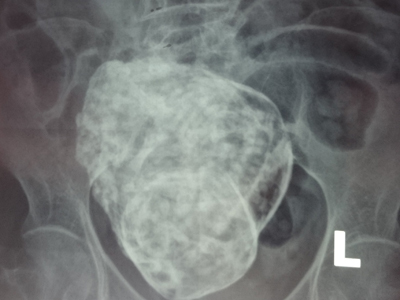

Tại hội chẩn, trên cơ sở kết quả chụp MRI: “Khối bất thường trong ổ bụng vùng hạ vị, ở sau bàng quang, có hình dạng giống thai nhi, khả năng thai vôi hóa. Chưa xác định được thai nằm trong ổ bụng hay trong tử cung trên hình ảnh MRI. Chẩn đoán phân biệt khối u quái (Teratoma)”. Chụp UIV, kết quả “Chức năng thận hai bên bình thường, hai niệu quản và bàng quang bình thường; xét nghiệm chức năng đông máu bình thường”.

| Hình ảnh "thai đá" được hội chẩn trong ổ bụng cụ bà 76 tuổi. |

Các bác sĩ đã nhận định, bệnh nhân vào viện vì đau lưng, hình ảnh phim X-quang và MRI cho thấy cột sống thắt lưng tăng độ cong về phía trước và nghiêng bên phải, đây là nguyên nhân chính gây đau lưng.

Khám bụng thấy khối u cứng nằm ở tiểu khung, di động ít. Các ý kiến thảo luận thống nhất đây là trường hợp "thai đá" hiếm gặp. Tuy nhiên, vẫn còn tranh luận cho đây là ca thai trong ổ bụng, thai trong thai, hay thai chết lưu trong tử cung hoá đá?